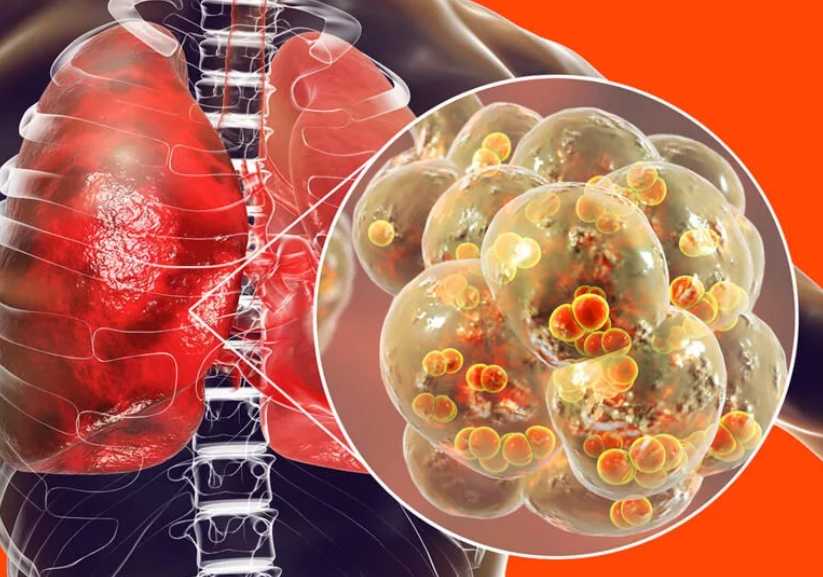

Заболевание развивается при поражении органов дыхания инфекцией, которая может быть бактериальной, вирусной, грибковой. Обычно у пневмонии бактериальная природа. А развивается недуг из-за:

Пневмония появляется при простуде, гриппе, бронхите, может развиваться в качестве самостоятельного недуга. Чаще всего наблюдается в случае слабого иммунитета. Ее нередко выявляют у детей и пожилых людей.

Коронавирус переходит в нижние дыхательные пути, поражает альвеолы легких. Начинается воспаление. Это нарушает газообмен, приводит к одышке. Даже после восстановления от пневмонии у человека может длительное время оставаться дыхательная недостаточность.

Пневмония при коронавирусе – распространенное явление. Причем многие болезненные симптомы могут быть незаметными. Проблема усложнена большим количеством очагов воспаления в легочной ткани с блокировкой альвеол легких. В данном случае необходима своевременная медицинская помощь.